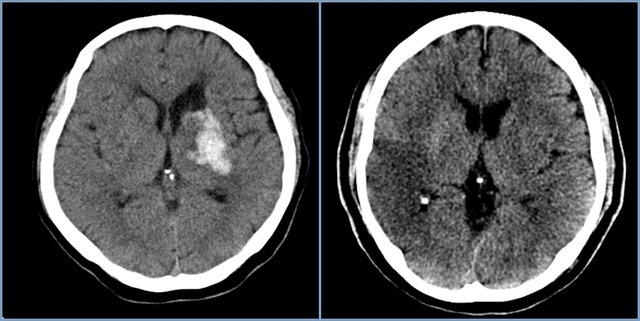

뇌경색 초기증상에 대하므로 살펴볼게요니다. 뇌에도 혈관이 있어서 피가 흐르고 있어요. 뇌에 있는 혈관이 막혀서 뇌의 일부가 손상되는 것을 뇌경색이라고 말해요. 뇌혈관이 막혀 뇌가 손상되면 장애가 발생할수 도 있으므로 뇌 연관 질환은 각별한 주의가 필요해요.

뇌에 제공되는 혈액량이 줄어들게면 뇌가 수습해야 되는 역할들을 제대로 실행해 낼 수 없게 돼요. 뇌혈류가 연속적으로 감소되면 뇌조직에 괴사가 시작되고 괴사된 뇌조직이 회복 불가능한 상태가 되면 뇌경색이라고 진단을합니다. 그러므로 뇌경색 초기증상을 알아두고 방지해억제해하시는게 중요해요.

뇌경색은 병에 걸려 후 얼마나 빨리 치료를 착수하는지에 따라 병의 증세가 결심되기도 합니다. 증상이 발생하면 아주많이 빨리 병원을 가서 초급성기 치료를 받아야합니다. 급성기 치료 후에는 이유가 되는 것에 따라 재발 방지를 위한 치료를 하게 되며 후유증에 대한 재활치료도 가능한 한 빨리 실행하는는게게 좋바람직해요. 증상이 처음 나타난 후 4~5시간이 경과하지 않으신다면 주사 제제를 통한 혈전용해술을 시도해 볼 수 있어요. 그리고 24시간이 경과하지 않았고 대뇌혈관이 막힌 것을 확인했으면 막힌 혈관에 대하여서 스텐트 투여술과 같은 기계적 재개통술을 시도할 수 있습니다.